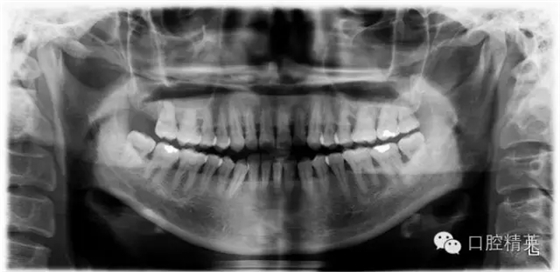

檢查見大量齦上及齦下結(jié)石,探診出血,牙周袋較深,32-42 II度松動。X線片顯示牙槽骨水平吸收。

X-ray: